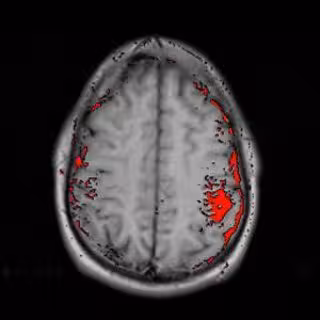

La mayoría de interfaces cerebrales diseñados para leer pensamientos requieren adiestramiento. Por ejemplo, para decir que sí, la persona necesita llevar a cabo una tarea mental prefijada como cantar una canción en su mente. Sin embargo, los nueve niños de este estudio no recibieron aprendizaje. Mediante una cinta colocada en la cabeza con fibra óptica que emite luz hacia el cortex prefrontal del cerebro, se les mostró dos bebidas en una pantalla de ordenador. "Cuando el cerebro está activo, el oxígeno en la sangre se incrementa y, en función de su concentración, absorbe más o menos luz", indicó Luu. "En algunas personas, sus cerebros son más activos cuando no les gusta algo, y en otros se hace más activo si es al contrario".

Tras programar al computador para reconocer un patrón único de actividad cerebral asociado a la preferencia de cada sujeto, los investigadores pudieron predecir de forma exacta qué bebida era la preferida en un 80 por ciento de los casos". La prefeencia es la base de las decisiones cotidianas", señala esta experta, quien señala que los niños discapacitados que no pueden hablar o gesticular para controlar sus movimientos, ellos pueden desarrollar falta de apoyo al aprendizaje que impide su desarrollo. Asi, esta especialista cree que podrá llegar a fabricarse un sensor portátitl basado en luz infrarroja que pueda llevarse en la cabeza y que gracias a tecnología sin cables, pueda permitir que estos niños puedan tomar decisiones.